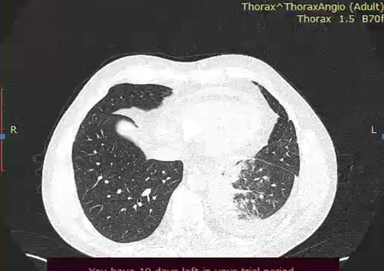

Computerized tomography suggested carcinomatous lymphangitis, without excluding primary origin and multiple lytic lesions of the skeleton. The radiologist suggested endoscopic examination.

Figure 1. CT images of lungs where carcinomatous lymphangitis was suggested.